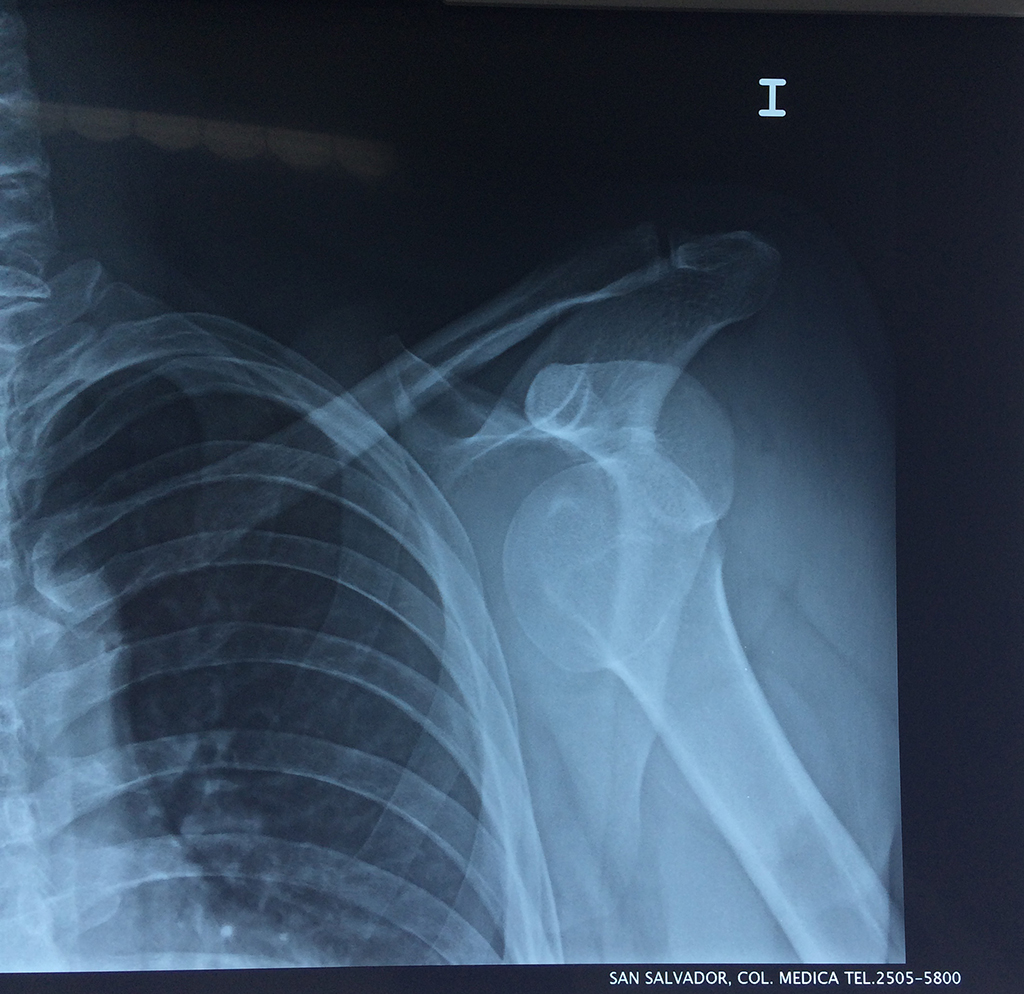

En anatomía humana, el hombro es la parte del cuerpo donde se une el brazo con el tronco. Está formado por la conjunción de los extremos de tres huesos: la clavícula, la escápula y el húmero; así como por músculos, ligamentos y tendones.

La principal articulación del hombro es la que une la cabeza del húmero con la escápula, recibe el nombre de articulación escapulohumeral y presenta dos superficies articulares, una de ellas corresponde a la cabeza del humero que tiene forma semiesférica y la otra es la cavidad glenoidea de la escápula, estas superficies están recubiertos por cartílago que permiten un movimiento suave e indoloro.

Exteriormente una envoltura de tejido blando circunda el conjunto, es la llamada cápsula articular que está reforzada por varios ligamentos que le dan estabilidad e impiden que los huesos se desplacen más allá de sus límites fisiológicos. Un conjunto de músculos y sus tendones se unen a las superficies de los huesos y hacen posible la movilidad de la articulación, entre ellos es muy importante el manguito rotador formado por cuatro músculos que proporcionan movilidad y estabilidad al hombro.